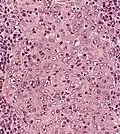

![]() | |

| Micrograph showing a nasopharyngeal carcinoma positive for Epstein-Barr virus-encoded small RNAs (EBER). | |

Nasopharyngeal carcinoma, also known as nasopharyngeal cancer, is classified as a malignant neoplasm, or cancer, arising from the mucosal epithelium of the nasopharynx, most often within the lateral nasopharyngeal recess or fossa of Rosenmüller (a recess behind the entrance of the eustachian tube opening). The World Health Organization classifies nasopharyngeal carcinoma in three types, in order of frequency: Non-keratinizing squamous cell carcinoma; keratinizing squamous cell carcinoma; and basaloid squamous cell carcinoma.[15] The tumor must show evidence of squamous differentiation; with the non-keratinizing type (also known as lymphoepithelioma), the tumor is most strongly associated with Epstein–Barr virus infection of the cancerous cells.[16]